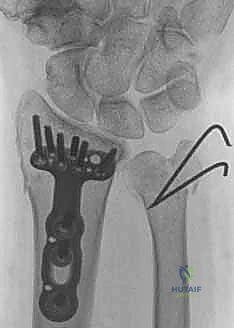

ثانياً: العلاج الجراحي (Surgical Intervention)

متى يقرر الدكتور هطيف ضرورة التدخل الجراحي؟

1. عدم الاستقرار (Instability): إذا كان المفصل الزندي الكعبري البعيد (DRUJ) غير مستقر بعد تثبيت كسر الكعبرة.

2. الانزياح (Displacement): إذا كان الكسر في قاعدة الناتئ الإبري منزاحًا بأكثر من 2 ملم.

3. الكسور المفصلية: أي كسر يخل بتطابق السطح المفصلي لرأس الزند.

4. الكسور المفتتة: في الجزء الكردوسي التي تؤدي إلى قصر عظم الزند.

صورة طبية: علاج كسور عظم الزند: دليل شامل لكسور الناتئ الإبري، الرأس، والجزء الكردوسي الكردوسي مع الأستاذ الدكتور محمد هطيف في صنعاء